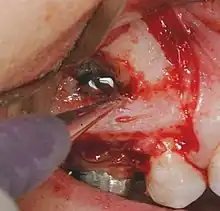

Résection apicale

Les objectifs de la résection apicale sont :

- retirer une partie de la racine qui ne pourrait être désinfectée ou/et remplie avec un matériau de remplissage de canal et dont les contenus peuvent avoir causé ou maintenu une inflammation,

faciliter l'accès pour la création d'une préparation de terminaison radiculaire, en vue d'un remplissage de terminaison radiculaire. L'apex doit être réséqué avec peu ou pas de biseau. Le procédé lui-même est rarement utilisé, et seulement quand on a considéré que le canal radiculaire a été traité de façon satisfaisante, et bien rempli.

- Préparation et remplissage de terminaison radiculaire

La préparation de la terminaison radiculaire est pratiquée après la résection de l'apex. Cela doit suivre les contours du système canalaire et être dans l'axe du (des) canal(aux). L'objectif du remplissage de terminaison canalaire est de remplir cette cavité et de fermer toute communication du canal radiculaire aux tissus péri radiculaires. Un matériau de remplissage est placé dans la cavité de la terminaison radiculaire. L'amalgame n'est plus le matériau de choix.